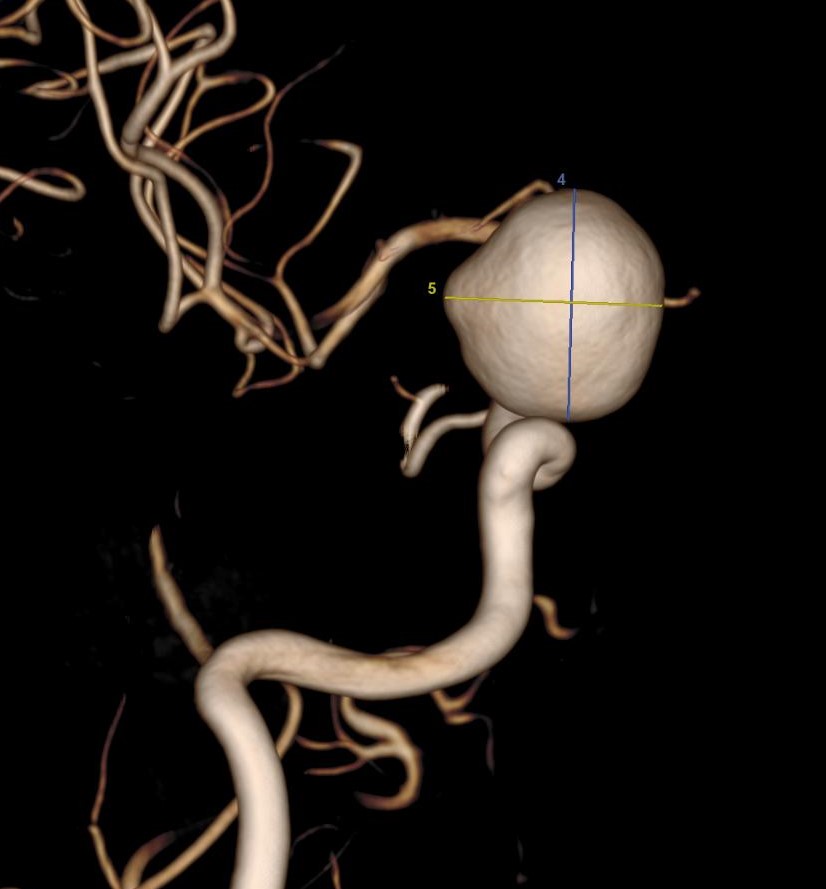

L’artériographie cérébrale est utilisée pour diagnostiquer des pathologies vasculaires, tels que les anévrismes intracrâniens, les malformations ou fistules artério-veineuses, les vascularites et les sténoses artérielles. Il s’agit d’un acte interventionnel à visée diagnostique. L’extrême précision des images permet aux médecins de comprendre en détail et en 3D l’état vasculaire du patient et de décider des meilleures options de traitement.

L’artériographie cérébrale est la méthode la plus précise et l’examen de référence pour diagnostiquer les pathologies des vaisseaux sanguins du cerveau. Elle permet un diagnostic détaillé des affections vasculaires cérébrales, bien plus fin que d’autres techniques d’imagerie comme l’IRM ou le scanner. Grâce à sa haute résolution spatiale, elle est particulièrement efficace pour guider les traitements, comme l’embolisation d’un anévrisme.